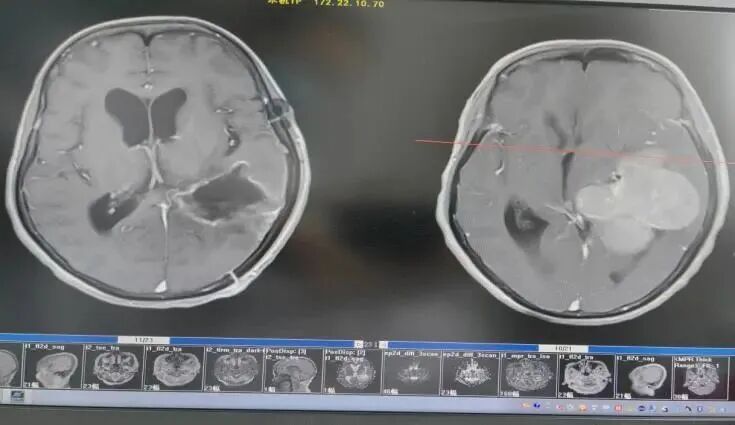

王阿姨今年70歲,最近兩個(gè)月總感覺(jué)四肢無(wú)力、頭痛頭暈,口服藥物治療后無(wú)明顯好轉(zhuǎn),后經(jīng)人介紹來(lái)到惠州市第三人民醫(yī)院,找到了神經(jīng)外科專(zhuān)家文世宏主任醫(yī)師。經(jīng)過(guò)專(zhuān)家的評(píng)估及,建議行頭顱核磁檢查,結(jié)果提示:左側(cè)顱內(nèi)巨大占位性病變,考慮是腦膜瘤。

由于腫瘤位置較深,且累及功能區(qū),周?chē)苌窠?jīng)分布復(fù)雜,手術(shù)難度非常大。手術(shù)中既要切除腫瘤,又不能損傷周?chē)匾纳窠?jīng)功能,極其考驗(yàn)醫(yī)生的技術(shù)與能力。為保證手術(shù)效果和王阿姨的安全,經(jīng)過(guò)學(xué)科討論,神經(jīng)外科團(tuán)隊(duì)最終為王阿姨制定了術(shù)中電生理監(jiān)測(cè)下實(shí)施“雙鏡聯(lián)合”的手術(shù)方式。

由于患者左側(cè)巨大顱內(nèi)占位,腫瘤血供較豐富,神經(jīng)外科團(tuán)隊(duì)術(shù)前認(rèn)真討論并做好充分術(shù)前準(zhǔn)備,先為患者行DSA造影,對(duì)腫瘤供血?jiǎng)用}進(jìn)行栓塞,以減少術(shù)中出血。

醫(yī)生術(shù)中發(fā)現(xiàn),腫瘤質(zhì)地較韌,血供極豐富!腫瘤血管被栓塞后,主刀醫(yī)生李雪松博士,助手文世宏主任醫(yī)師、劉惜弟主治醫(yī)師先在顯微鏡下分塊切除腫瘤,然后使用神經(jīng)內(nèi)鏡進(jìn)行內(nèi)部探查腫瘤是否全切及是否有出血。為完整切除腫瘤,最大限度地減少對(duì)腦組織的損傷,手術(shù)團(tuán)隊(duì)密切配合并執(zhí)行精準(zhǔn)操作。經(jīng)過(guò)4小時(shí)的奮戰(zhàn),腫瘤被全部切除!